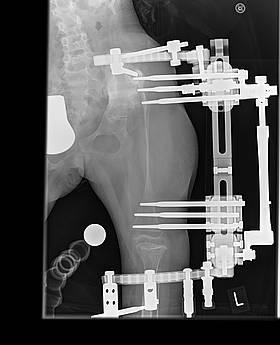

Die Anfangszeit der Verlängerung verlief einwandfrei. Wir konnten ohne Drehpause 3 1/2 Monate lang verlängern. Insgesamt schafften wir 8,3 / 8,4 cm Verlängerung. Das linke Bein war im Januar ein kleines Stückchen länger als das rechte Bein. Doch dann begann das Drama. Lea bekam eine eitrige Entzündung der Beckenpins nach der anderen. Der Knochen begann dünner zu werden. Die Beckenpins lockerten sich. Durch das lockern der Beckenpins, konnte sich der Oberschenkel ein kleines Stückchen ins Becken bohren. Im Juni kam dann die nächste OP. Leas 3 Beckenpins, die ständig eitrig entzündet waren und sich massiv gelockert hatten kamen raus und sie bekam etwas oberhalb am Becken zwei neue Pins eingesetzt. Danach ging es wieder bergauf. Der Knochen baute sich zwar nicht wieder auf, aber er baute sich auch nicht weiter ab. Der amerikanische Spezialist empfahl uns eine Zometa Therapie, sowie spezielle Vitaminpräperate aus Amerika zu nehmen.

Unsere Ärzte trauten sich aufgrund der dünne des Knochens und der vorangegangenen Komplikationen nicht an die Entfernung des Fixateurs, so dass eine erneute Operation duch den Amerikaner notwendig wurde. Er hat den externen Fixateur am 01.10.2012 operativ entfernt und stabilisierte den Oberschenkel mit einer speziellen Lochplatte. Im oberen Oberschenkelbereich fixierte er diese mit 5 Schrauben, im unteren Oberschenkelbereich mit 3 Schrauben. Lea darf nun insgesamt 7 Wochen nicht belasten. Nur Liegen und Sitzen.